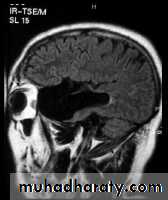

ARACHNOID CYST :

-clear csf filled cyst.

- occur due to congenital splitting of the arachnoid membrane.

- they are intracranial but extracerebral.

-cam be seen in middle ,posterior cranial fossa , suprasellar region & behind the 3rd ventricle.

- they can be large enough to produce mass effect or obstructive hydrocephalus.

- there may be Hypoplasia of underlying cerebral tissue such as the temporal pole.

Sagittal fluid-attenuated inversion recovery (FLAIR) weighted image through a brain lesion), showing homogeneity of the lesion, lack of a perceptible wall, lack of internal complexity, and CSF signal intensity. There is associated brain displacement. These imaging features are typical of an arachnoid cyst.